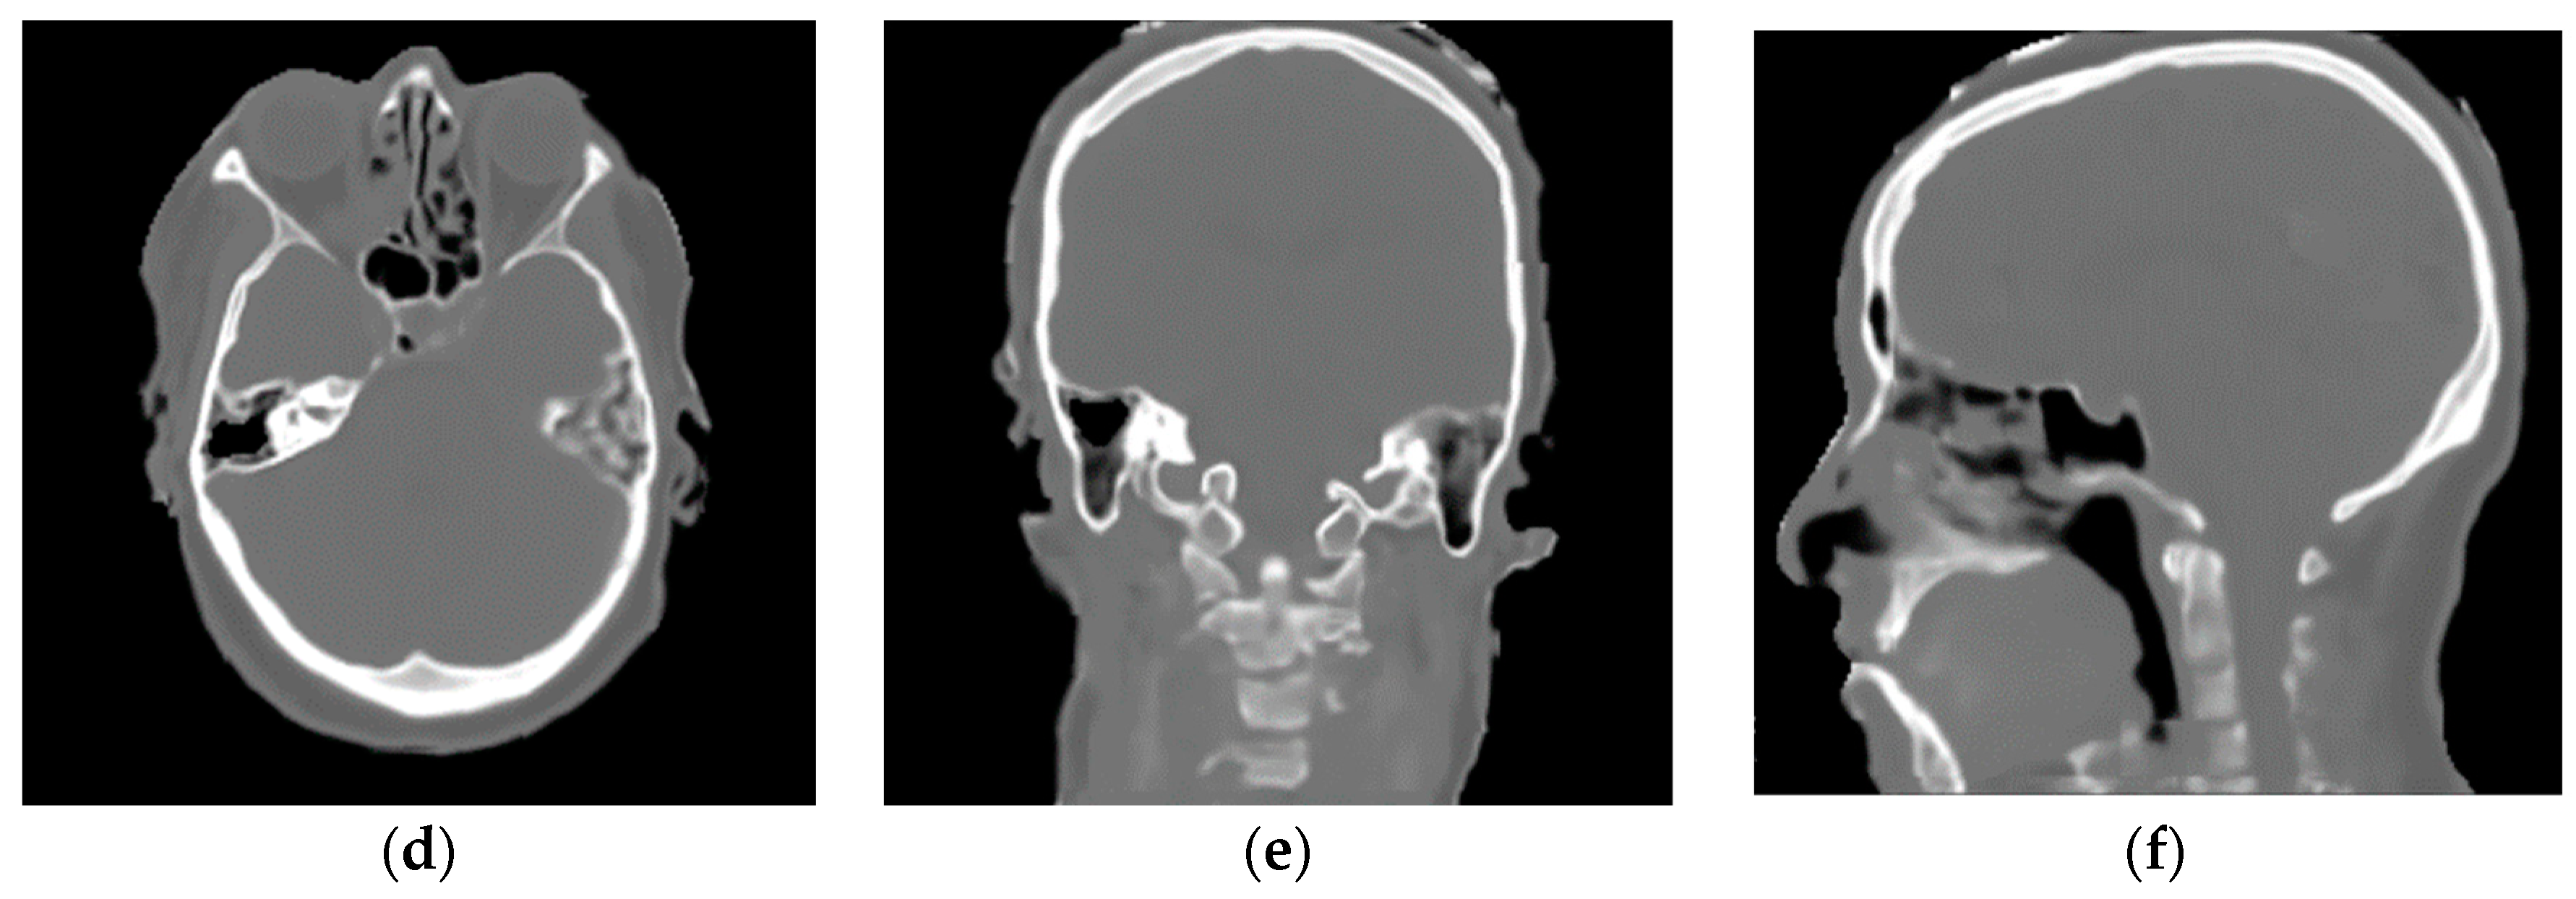

2.2.1. Training Dataset

2.2.2. Validation Dataset

3.1. Convolutional Neural Network (CNN) Results

3.2. Franken-CT Approach Results